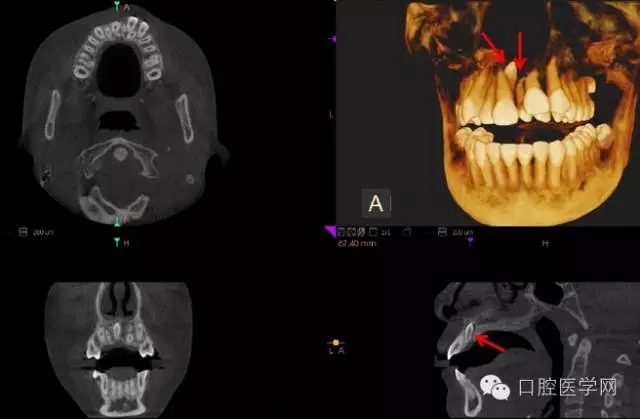

4.阻生牙

最常見于下頜第三磨牙

X線表現(xiàn):確定阻生牙的位置;確定阻生方向;牙根數(shù)目和形態(tài);阻生牙有無齲齒和根尖情況;與第二磨牙的關(guān)系;與下頜管的距離和磨牙后間隙的大小。